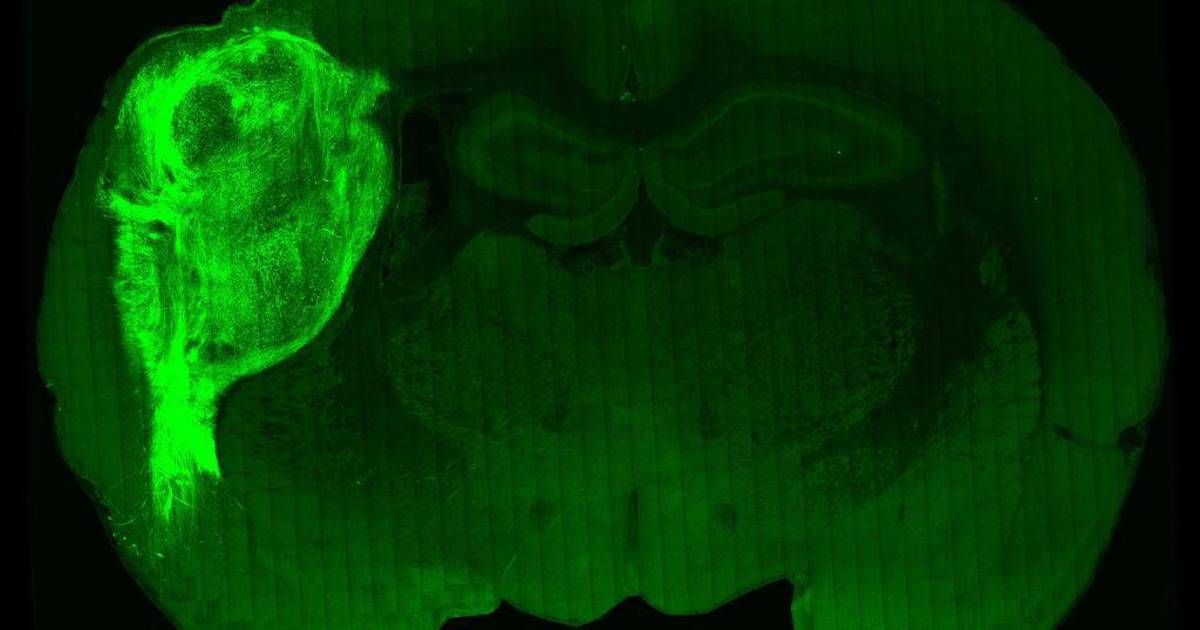

Para evitar estas limitaciones, los científicos implantaron estos tejidos de cerebro humano, llamados organoides, en el cerebro de ratas jóvenes. La edad era importante puesto que el cerebro de un animal adulto deja de desarrollarse, lo que habría afectado a la integración de las células humanas.

Al trasplantarlos a un animal joven, “constatamos que los organoides pueden volverse bastante grandes y vascularizados” y pueden entonces estar alimentados por la red sanguínea de la rata, hasta “ocupar alrededor de un tercio del hemisferio del cerebro” del animal, detalla el profesor Pasca.